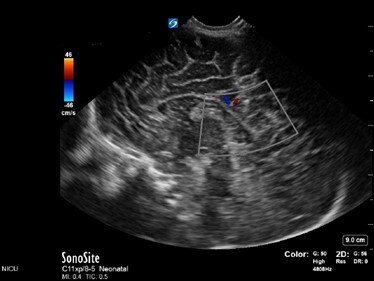

Neonatology Normal Anatomy High Velocity Image